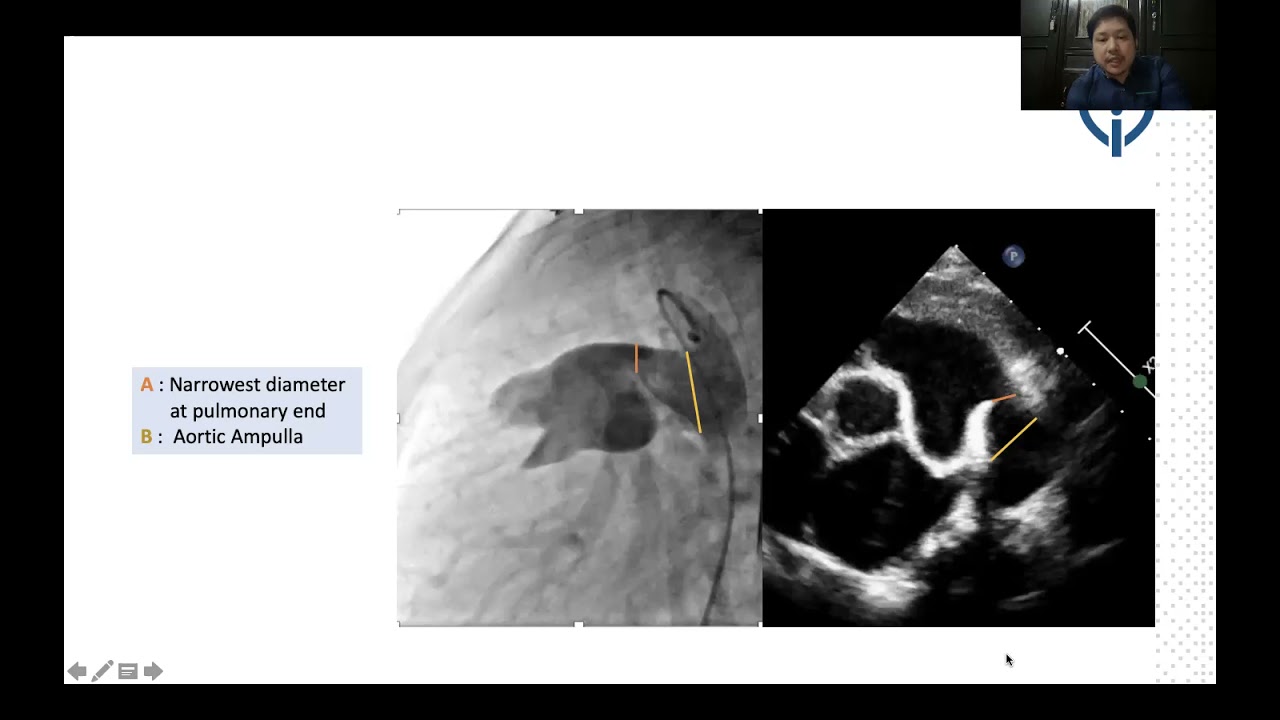

Is there a transcatheter solution for hypoplastic right heart syndrome? : pulmonary valve perforation in a neonate with pulmonary atresia, restrictive VSD and a small right ventricle

By: Sanjeev Hanumantacharya Naganur, Chandigarh, India